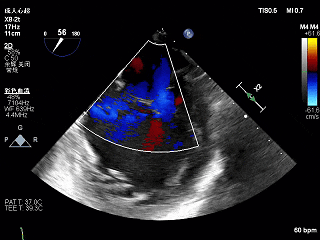

术前Bicom切面

术前X-Plane

3D-ZOOM 彩色多普勒显示反流主要来源于2区